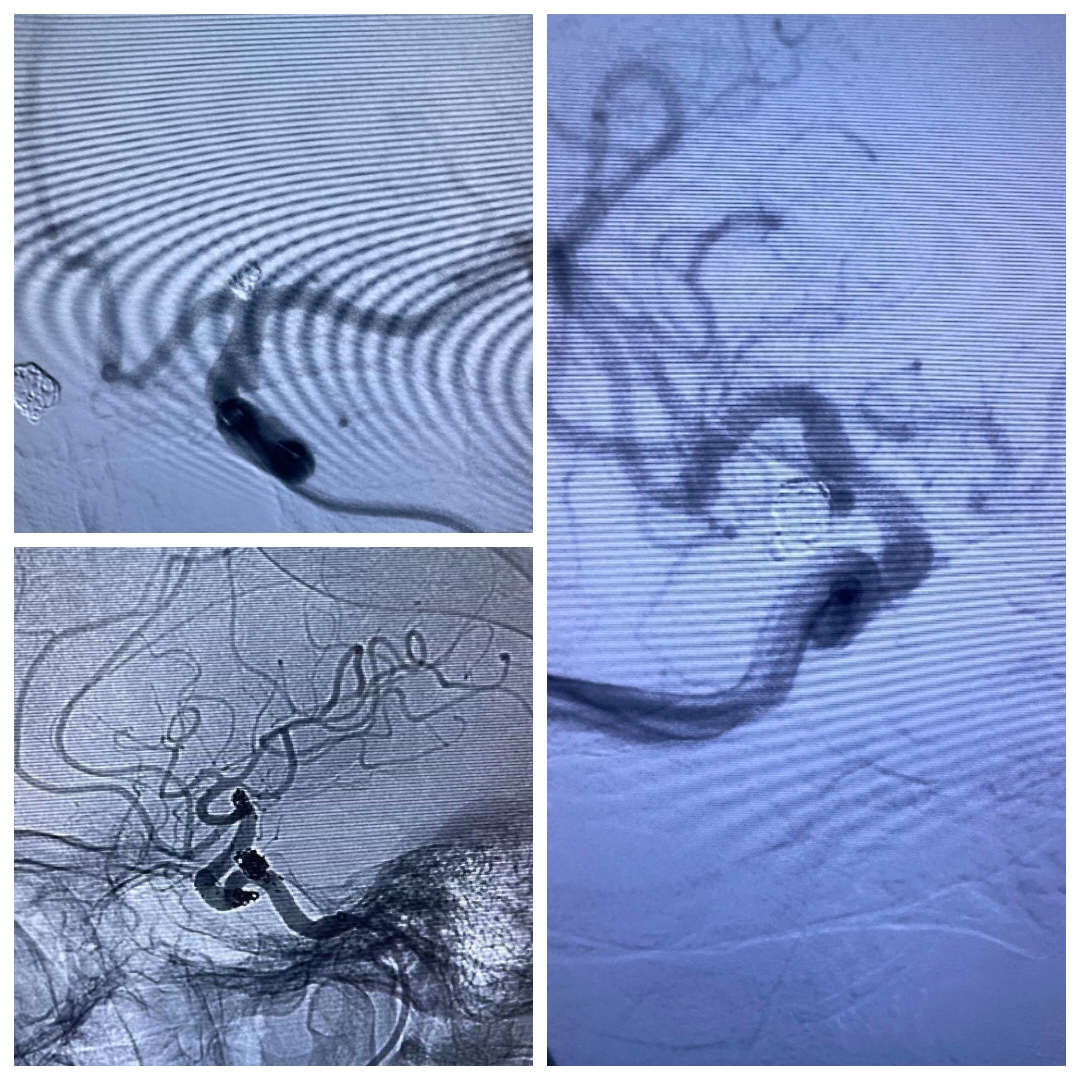

病例二、颅内动脉瘤破裂出血(介入栓塞治疗)

吴某某,56岁,女性,因“右侧眼睑下垂一周”入院

查体:神志清,右眼瞳孔4mm,对光反射消失,右眼睑下垂

DSA提示右侧后交通动脉瘤,左侧颈内动脉末端动脉瘤,左侧后交通圆锥,左侧海绵窦夹层动脉瘤。

下面这个动脉瘤像不像一颗爱心,可是它很“凶残”。随时可能破裂出血,危急患者生命。

我们术中先解决右侧后交通责任动脉瘤,再解决左侧颈内动脉末端以及海绵窦夹层动脉瘤,手术顺利,动脉瘤消失,可谓一箭三雕🐮!